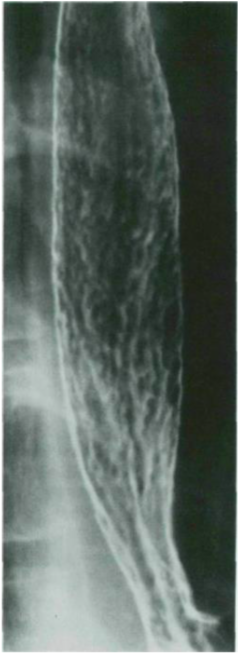

A 38-year-old male presented with a 6-month history of heartburn and epigastric pain aggravated especially after eating spicy food and on lying down. He doesn’t have dysphagia, odynophagia, or weight loss. Barium swallow X-ray was performed. Which of the following is the next step in his management?

A. Upper GI endoscopy

B. Therapeutic trials of acid suppression